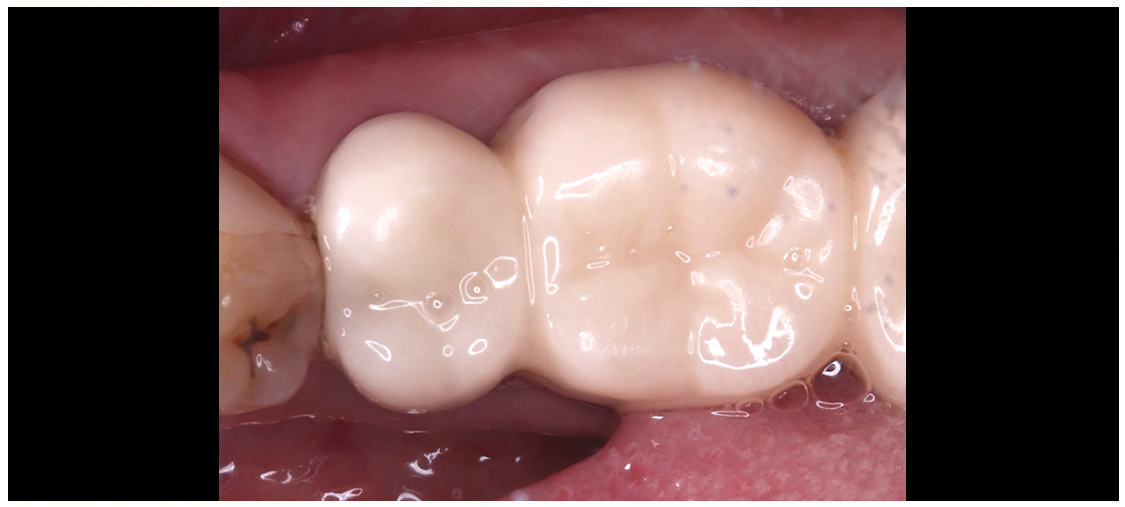

クラウン

ジルコニアクラウン エコノミー

(レイヤーブロック)

ジルコニアクラウン スタンダード(ステイン)

ジルコニアクラウン プレミアム

オールセラミッククラウン

ゴールドクラウン